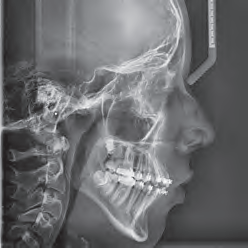

Das PaX-i Plus AI ist ein modernes digitales Panorama-Röntgensystem (OPG), das innovative Bildgebung mit künstlicher Intelligenz verbindet. Es wurde entwickelt, um Diagnosen zu präzisieren, Arbeitsabläufe zu optimieren und die Patientenversorgung nachhaltig zu verbessern.

Dank leistungsstarkem CMOS-Sensor, intelligenter Bildoptimierung und automatisierten Funktionen liefert das System zuverlässig hochwertige Aufnahmen – auch unter anspruchsvollen Bedingungen. Die modulare Bauweise sowie die einfache Integration in bestehende Praxissoftware machen das PaX-i Plus AI zu einer zukunftssicheren Lösung für Zahnarztpraxen und Kieferorthopäden.

Hochauflösende Panoramaaufnahmen

Schnelle kephalometrische Aufnahmen